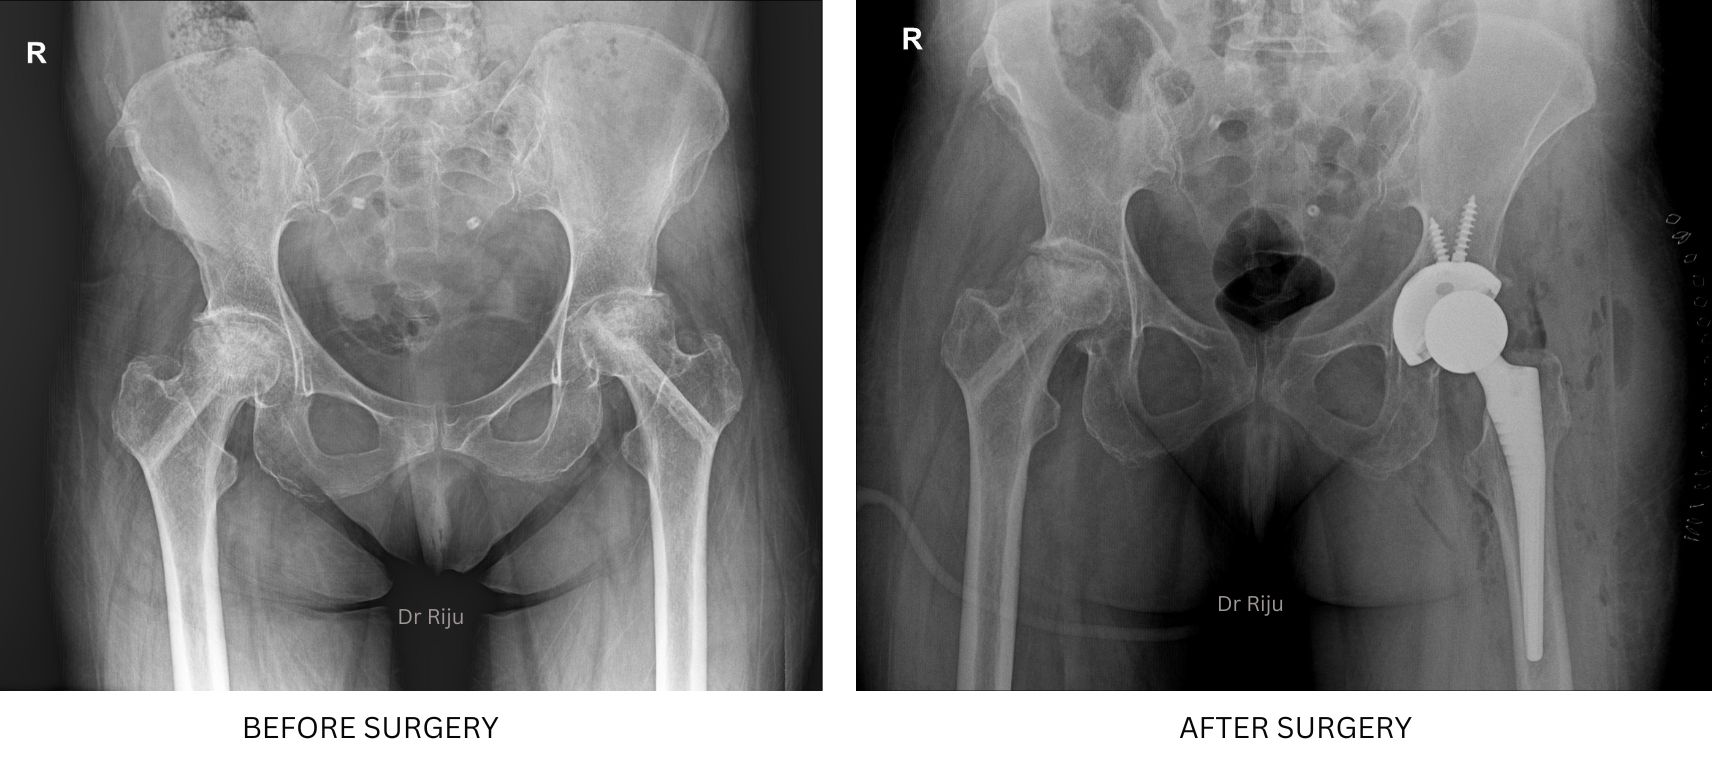

Image Gallery